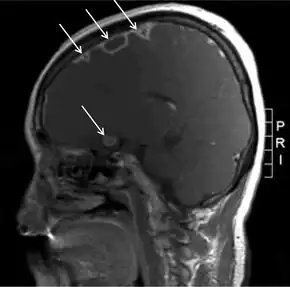

During the primary infection, F. necrophorum colonizes the infection site and the infection spreads to the parapharyngeal space. The bacteria then invade the peritonsillar blood vessels where they can spread to the internal jugular vein.[6] In this vein, the bacteria cause the formation of a thrombus containing these bacteria. Furthermore, the internal jugular vein becomes inflamed. This septic thrombophlebitis can give rise to septic microemboli[12] that disseminate to other parts of the body where they can form abscesses and septic infarctions. The first capillaries that the emboli encounter where they can nestle themselves are the pulmonary capillaries. As a consequence, the most frequently involved site of septic metastases are the lungs, followed by the joints (knee, hip, sternoclavicular joint, shoulder and elbow[13]). In the lungs, the bacteria cause abscesses, nodulary and cavitary lesions. Pleural effusion is often present.[7] Other sites involved in septic metastasis and abscess formation are the muscles and soft tissues, liver, spleen, kidneys and nervous system (intracranial abscesses, meningitis).[6]

Chest X-ray and chest CT may show pleural effusion, nodules, infiltrates, abscesses and cavitations.